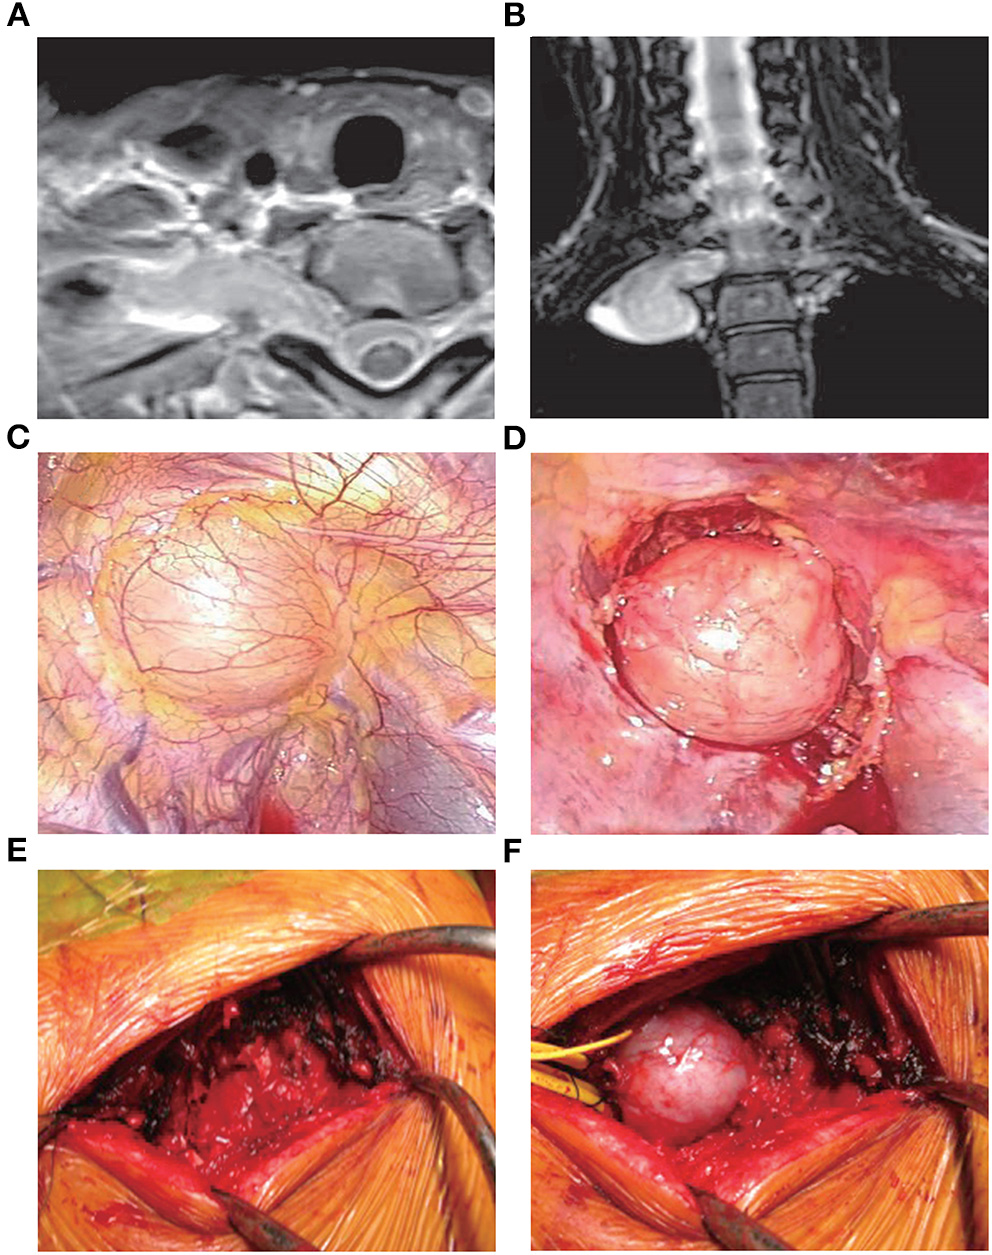

VATS has been widely used in cardiothoracic surgery, and its advantages have been demonstrated (22). The limited damage to the thorax and clear images of the location of the tumors associated with this approach render VATS a suitable option for the treatment of MST. Of note, its advantages become more obvious when applied to the upper thoracic spine (Figure 2) (23, 24).

Figure 2

Treatment with VATS (25). A 41-year-old female presented with an abnormal shadow on the apical portion of the right lung and motor weakness of the intrinsic muscle in her right hand. Examination revealed the presence of a dumbbell tumor of the right T1 nerve root, extending to the foramen and paravertebral region. Due to her symptomatic presentation, the patient underwent VATS along with posterior spinal surgery. Initially, anterior release using VATS in the left lateral position was performed. During posterior spinal surgery following VATS, a response to intraoperative nerve stimulation on the T1 nerve root distal to the tumor was confirmed. Therefore, enucleation of the tumor was performed using an operating microscope to preserve the function of the intrinsic muscle. (A,B) Magnetic resonance imaging images showing the presence of a dumbbell tumor at the right T1 nerve root, extending to the foramen and paravertebral region. (C) The tumor during VATS. (D) The tumor after the anterior release of the ambient organs. (E) Partial costotransversectomy was performed following VATS. (F) The preceding VATS ensured tumor mobility in the prone position. The tumor was moved to the surface through gentle handling. VATS, video-assisted thoracoscopic surgery.

In 2008, Kan et al. (26) studied five MST patients who underwent tumor excision through a minimally invasive thoracoscopic approach. In all patients, pain and neurological deficits were significantly improved during the 4–6 months of follow-up. However, Huang et al. (27) indicated a 12% rate of excessive bleeding among 41 MST patients treated with thoracoscopic corpectomy. This finding suggests that this approach may be associated with a significant risk of bleeding.